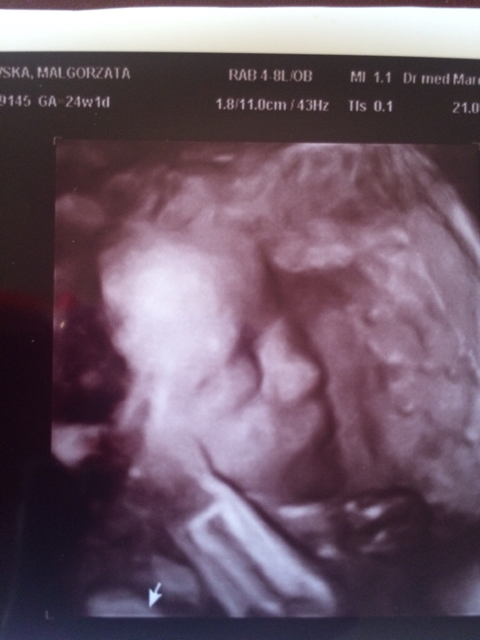

Ja po wizycie, jutro mam zrobic proby,choc ponoc na cholestaze to za szybkoi przyjsc w piatek z wynikami.

1474475197-ilh13q.jpeg